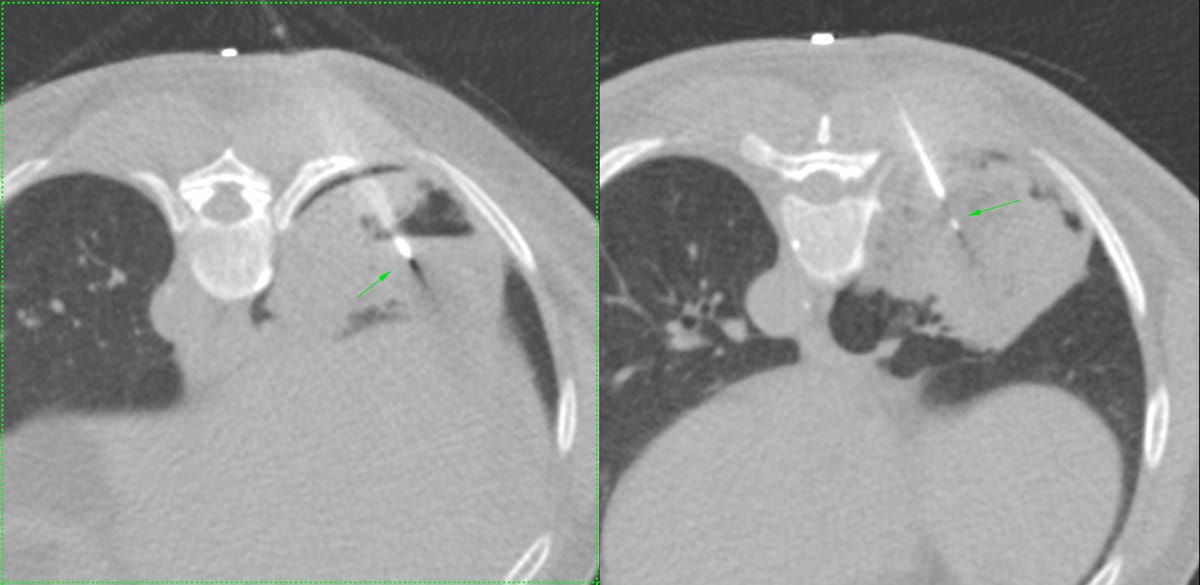

59-years old with fever and non-resolving consolidation

What would be your approach?

The video below describes the case and the reason for performing a biopsy parallel to the vessels and not perpendicular